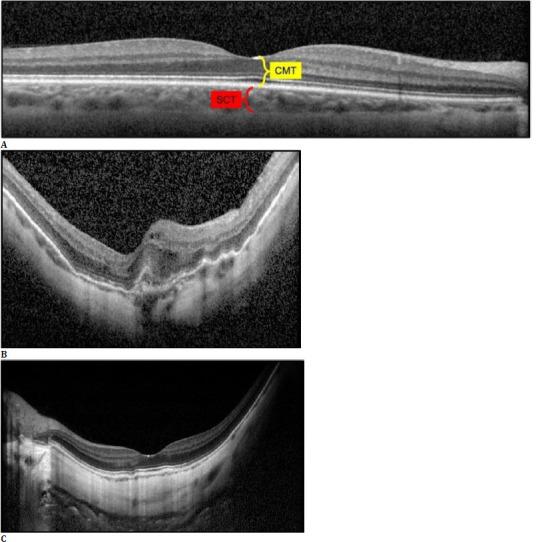

A total of 122 eyes from 78 patients were included. Seventy-five eyes with an AL ranging between 26.00 and 27.49 mm comprised Group 1, and 47 with an AL of ≥ 27.50 mm comprised Group 2. Spectral-domain OCT was performed to measure the central macular thickness, subfoveal choroidal thickness (SCT) and swept-source OCTA was utilized to obtain the data on foveal avascular zone (FAZ) and vascular density (VD) values at the superficial and deep capillary plexuses (SCP and DCP), outer retina (OuR), and choriocapillaris (CC) segments.

材料与方法